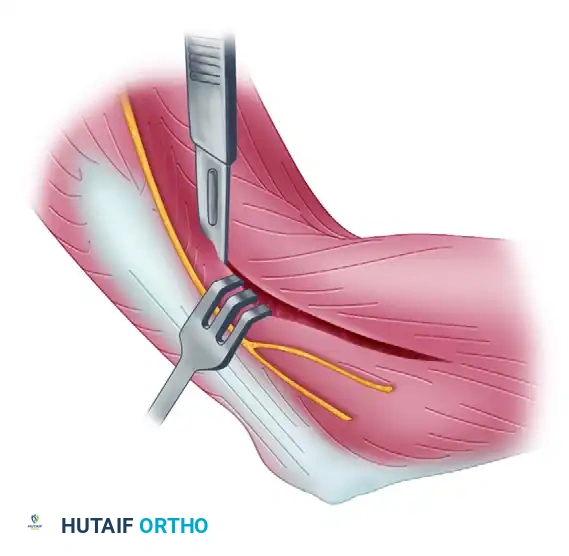

The goal of the anterior dissection is to safely separate the neurovascular structures from the anterior capsule before performing the capsulectomy.

- Carefully elevate the brachialis muscle belly off the anterior joint capsule. This must be done meticulously, as the brachialis serves as a protective barrier for the brachial artery and the median nerve.

- Place blunt retractors (such as right-angle or Hohmann retractors) deep to the brachioradialis and brachialis muscles. This maneuver safely retracts the anterior neurovascular bundle and exposes the underlying, thickened anterior joint capsule.

- Perform a comprehensive anterior capsulectomy, proceeding systematically from lateral to medial.

- Critical Step: Identify and preserve the lateral collateral ligament (LCL) complex, specifically the lateral ulnar collateral ligament (LUCL). The capsulectomy must stay strictly anterior to the LCL origin on the lateral epicondyle to prevent iatrogenic posterolateral rotatory instability (PLRI).

Surgical Warning: When extending the anterior capsulectomy medially, maintain the dissection strictly within the capsular plane. Straying anteriorly risks injury to the median nerve and brachial artery, while straying too far medially and posteriorly risks injury to the ulnar nerve.